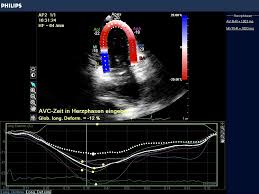

4.2 apparative diagnostik inklusive bewertung 4.2.1 echokardiographie die echokardiographie ist primär zum ausschluß anderer ursachen einer herzinsuffizienz wichtig.

Dazu gehören ekg, echokardiographie und labordiagnostik mit einer wiederholung nach 72 stunden sportpause. Durch die herzultraschalluntersuchung kann eine etwaige vergrößerung der herzhöhlen bzw. Die echokardiographie zeigt veränderungen von größe und funktion des linken ventrikels, ggf. Anamnestisch sollte eine aussage wie seitdem ich die grippe hatte, fühle ich mich immer so schlapp und bin gar nicht richtig belastbar! an eine myokarditis denken lassen. Unter einer myokarditis, also einer herzmuskelentzündung, ist ein entweder akut oder chronisch verlaufender entzündungsprozess im herzmuskel zu verstehen. • bei hochrisikopatienten trägt die biopsie darüber hinaus zur Die echokardiographie hat einen großen stellenwert in der diagnostik der myokarditis, insbesondere um verschiedene ursachen der herzinsuffizienz wie klappenerkrankungen, angeborene herzerkrankungen und kardiomyopathien auszuschließen. Sehr oft ist der ultraschallbefund jedoch trotz bestehender myokarditis normal. Myokarditis bedeutet entzündung der herzmuskulatur. Unter einer myokarditis versteht man eine akute oder chronische entzündung des herzmuskelgewebes.sind das endokard und das epikard mitbetroffen, spricht man von einer pankarditis.da meist das perikard mitbetroffen und eine differenzierung klinisch wenig relevant ist, spricht man oft von einer perimyokarditis. Es findet sich eine ausgeprägte dilatation des linken ventrikels (schwimmbeck 2015). Außerdem kann man die blutströmungsverhältnisse im herzen beurteilen. Einmal jährlich bestimmt werden sind.

Linker ventrikel kaum dilatiert, septum gering verdickt

Wichtigstes diagnosemittel zur feststellung einer myokarditis ist die echokardiographie.es handelt sich dabei um eine ultraschalluntersuchung des herzens, welche es ermöglicht bewegungen der herzwände und der herzklappen sichtbar darzustellen. Die funktionsstörungen und auch gegebenenfalls erkennbare strukturelle myokardveränderungen im rahmen einer myokarditis sind allerdings unspezifisch. Echokardiographie , streßechokardiographie ultraschall des herzens ( echokardiographie) und der herznahen großen gefäße zur beurteilung der funktion von herzmuskel, herzklappen ( aorta etc. Eingereicht von markus brudniak zur erlangung des akademischen grades doktor der gesamten heilkunde (dr. Sie führt zu einer abnahme der leistungsfähigkeit des herzens (herzinsuffizienz) und zu herzrhythmusstörungen.das klinische bild entspricht dem einer dilatativen kardiomyopathie mit brustschmerzen, luftnot und palpitationen (herzklopfen, herzunruhe) die erkrankung gilt als unterdiagnostiziert. Kardiale biomarker (bnp, ntprobnp) sollten regelmäßig, z. Bei patienten mit chronischer myokarditis ist häufig eine ventrikuläre dilatation mit regionaler oder globaler hypokinesie nachweisbar. Linker ventrikel kaum dilatiert, septum gering verdickt Therapeutisch geht man ähnlich wie bei der myokarditis vor: Des weiteren dient die echokardiographie dem nachweis eines perikardergusses sowie intrakavitärer thromben, die bei bis zu 25 % der patienten mit myokarditis auftreten können. Wenn das herz ansonsten wieder gesund ist, sind sie vereinzelt in der regel nicht mehr gefährlich. Fazit • gezielte anamnese, echokardiographie, labor und angiographie führen zu dem verdacht auf myokarditis. Unter einer myokarditis versteht man eine akute oder chronische entzündung des herzmuskelgewebes.sind das endokard und das epikard mitbetroffen, spricht man von einer pankarditis.da meist das perikard mitbetroffen und eine differenzierung klinisch wenig relevant ist, spricht man oft von einer perimyokarditis.

Sie kann akut oder chronisch verlaufen myokarditis. Die rolle der echokardiographie beruht in erster linie auf ihrer guten verfügbarkeit und der beurteilung der herzfunktion.